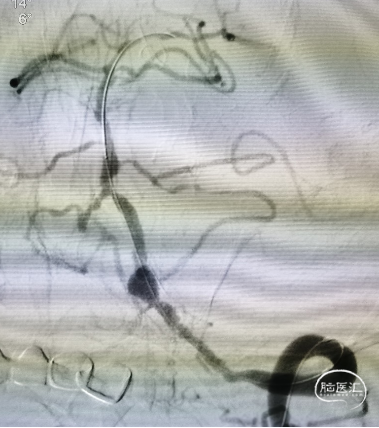

穿支架网眼动脉瘤近全栓塞(Target 360 Ultra 3 mm×6 cm、Target 360 Ultra 2 mm×6 cm

Gateway 2.0 mm×15 mm球囊命名压缓慢后扩支架

栓塞结束后造影情况,可见支架贴壁良好,血管狭窄较前改善,动脉瘤近全栓塞,远端大脑后动脉显影明显改善